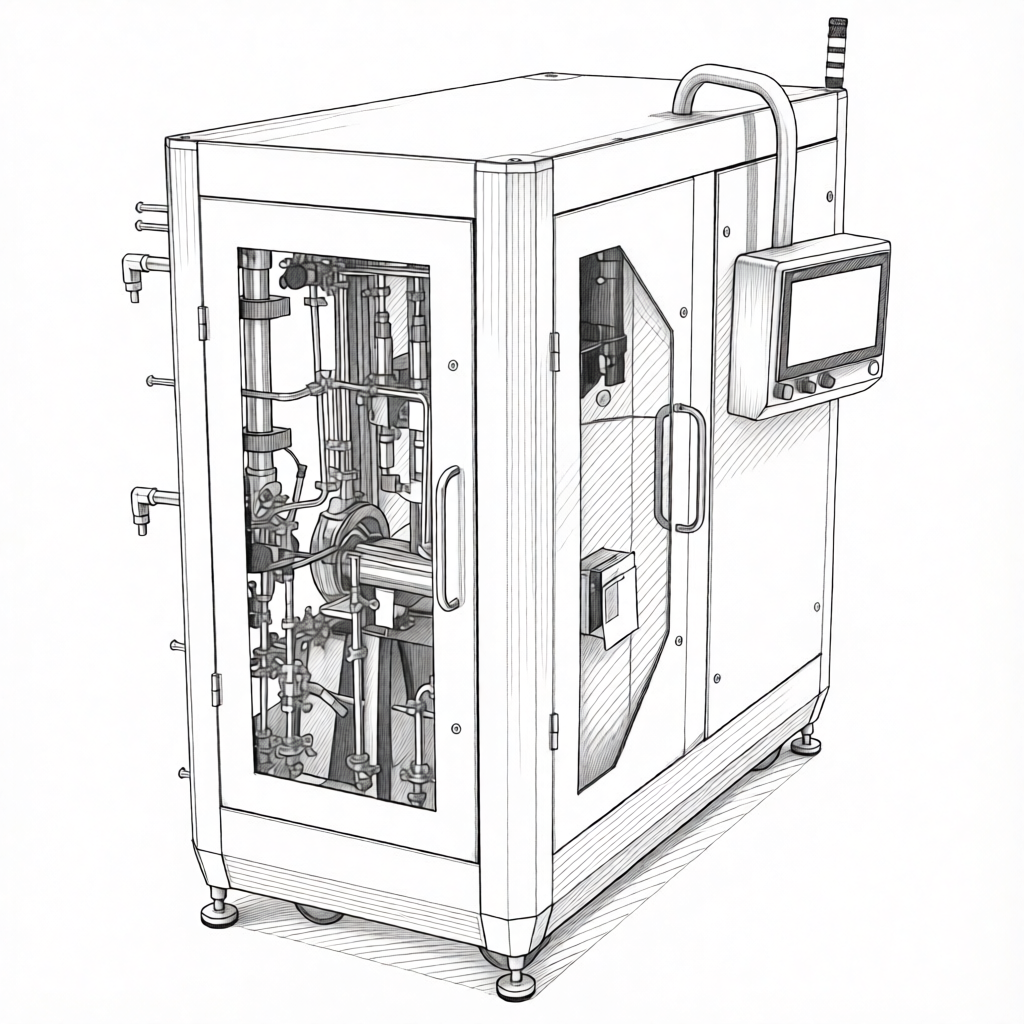

Fabricación en Contínuo

iXOLAB apuesta por la fabricación en continuo que representa una transformación paradigmática en la industria farmacéutica, sustituyendo la producción por lotes por un flujo ininterrumpido de materiales a través de todas las etapas: dosificación precisa, mezcla, granulación, compresión y recubrimiento operan de forma integrada y sincronizada.

Este modelo reduce drásticamente los tiempos —de días a minutos—, minimiza la huella física de las instalaciones y elimina inventarios intermedios. Su principal ventaja radica en el control de calidad en tiempo real mediante tecnologías analíticas de proceso (PAT).

La flexibilidad inherente facilita la producción ágil de volúmenes ajustados, beneficiando ensayos clínicos y medicamentos de nicho. Como columna vertebral de la farmacia 4.0, la fabricación continua habilita la integración de inteligencia artificial para optimización autónoma y trazabilidad completa, sentando las bases para una producción personalizada a escala.